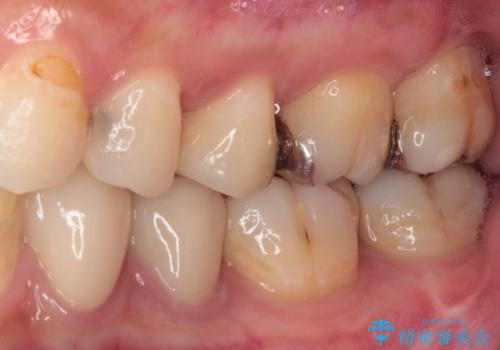

- 奥歯に頻繁に物が挟まるとのことで来院された患者様です。

最近ものが挟まりやすくなったり、冷たいものがしみるようになったりといった症状があり、診査したところ、むし歯や歯質の欠損、不適修復物などが認められました。

精度の高いセラミックインレーによる修復治療を行うこととしました。